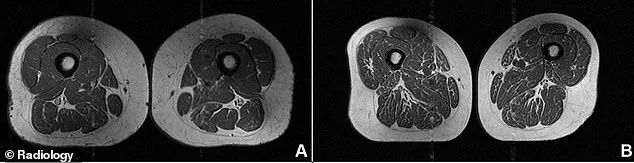

The visual evidence is stark when comparing MRI scans of two women of similar age and weight. A 61-year-old whose diet contains 30 percent ultra-processed foods shows minimal fat infiltration, whereas a 62-year-old whose diet is 87 percent ultra-processed foods shows significant, visible marbling.

White streaks of fat can replace healthy muscle, much like the marbling seen in a piece of steak. This internal infiltration occurs when diets rely heavily on ultra-processed foods, directly weakening the body's essential muscle tissue.

The study, published in the journal Radiology, utilized MRI scans to observe fat levels within the thighs. Researchers graded fat infiltration in the hamstrings, quadriceps, and inner thighs on a scale from zero to four, where four represents over 50 percent fat.